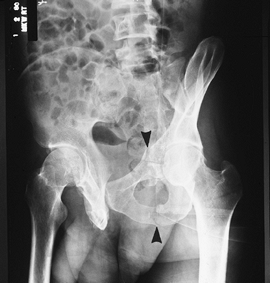

![]() |

FIGURE 4-5 Lateral compression injuries. (A) Type I: force applied posterolaterally (arrow)

resulting in a crush injury to the sacrum, ilium, and sacroiliac joint (1) and oblique or horizontal pubic rami fractures (2). (B) Type II: force directed anterolaterally (arrow) resulting in diastasis of the sacroiliac joint (1 and 3) (Type IIA) or iliac wing fracture (Type IIB) plus oblique or horizontal pubic rami fractures (2). (C) Type III: force applied anterolaterally (arrow) with oblique or horizontal pubic rami fractures (2) and involvement of both sacroiliac joints and ligaments (1, 3, and 4) (Type IIIA) or sacroiliac joints and ipsilateral iliac wing fracture (Type IIIB). |

FIGURE 4-6 AP compression injuries. (A) Type I: force applied anteriorly (arrow) resulting in diastasis of the pubic symphysis or vertical pubic rami fractures. (B)

Type II: wider diastasis of the pubic symphysis or vertical pubic rami fractures with disruption of the anterior sacroiliac ligaments. (C) Type III: wider diastasis of the pubic symphysis or displaced vertical pubic rami fractures with disruption of both the anterior and posterior sacroiliac ligaments. (D) AP compression injury with vertical pubic rami fractures. Sacroiliac joints are normal. Note the elevated bladder resulting from a large pelvic hematoma. Type I. (E) Type III AP compression injury with wide diastasis of the pubic symphysis, displaced iliac wing fracture (white arrow), widening of the right sacroiliac joint (black arrow), and multiple avulsion fractures (arrowheads). |